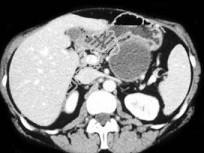

- 单项选择题如图所示,该病的鉴别诊断包括以下所有的, 除哪项以外 ( )

A、腺癌

B、Hamoudi瘤

C、囊腺瘤

D、胰腺导管内乳头状黏液性肿瘤

E、胰癌